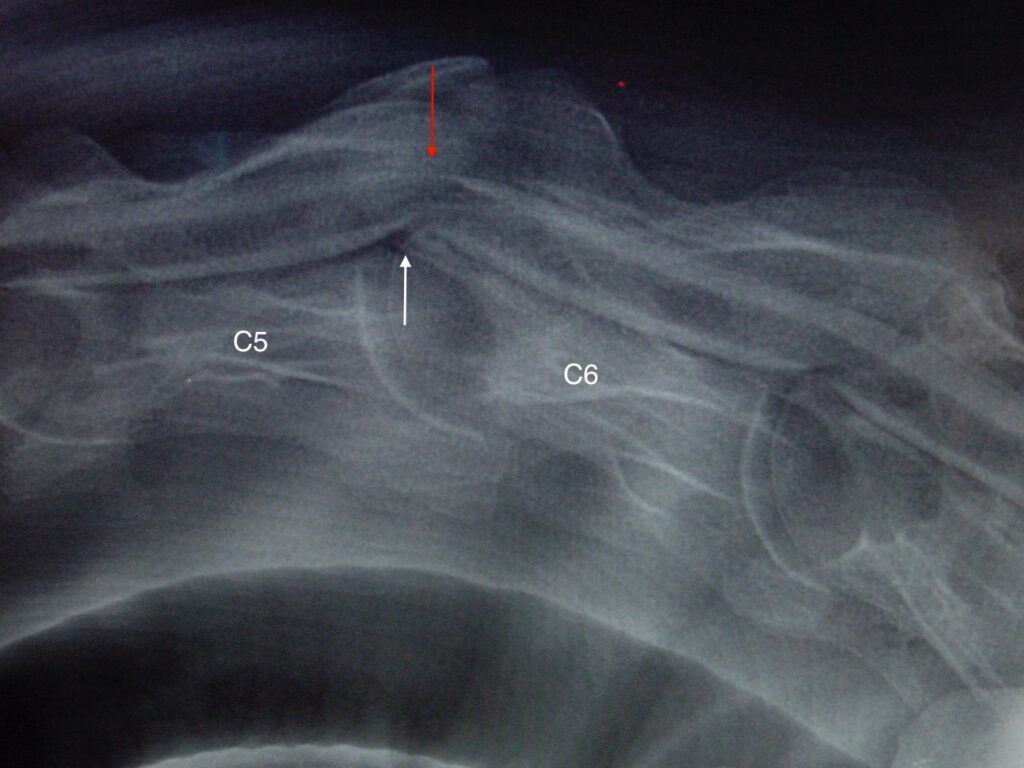

Obrázek 2a, b: Hříbě s ataxií a horečkou způsobenou zánětem kostí obratlů C6–C7. Na CT je jasně patrné výrazné poškození kostí v důsledku infekce (bílé šipky). Na obrázku 2b je stejný případ z jiného pohledu

Obrázek 2c: Postižená kost a meziobratlová ploténka byly chirurgicky odstraněny a oba obratle byly spojeny pomocí ploténky a šroubů